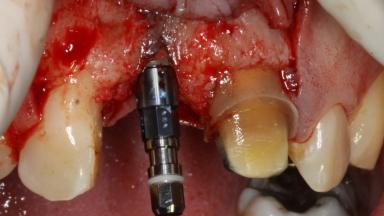

The patient presented with a failing tooth-supported fixed dental prosthesis with cantilever extension replacing the right maxillary central incisor. His chief presenting complaint was poor esthetics, in particular the dark discolored margin around the abutment tooth, the maxillary left central incisor. He reported a history of trauma at a young age, which necessitated the replacement of his maxillary right central incisor as well as root canal therapy of the adjacent left central incisor. The existing prosthesis had been in situ for over 20 years. The initial periapical radiograph displayed good proximal bone levels at the adjacent teeth and a wide incisive canal, which was a concern. The left central incisor presented a very wide root canal treatment with compromised radicular dentin thickness, which was a consideration in the decision between a new tooth-supported fixed dental prosthesis vs. an implant-supported prosthesis. After a lengthy discussion on the risks and benefits of both treatment options, the patient decided on a single-tooth implant replacement.

Bone Augmentation Simultaneous

Bone Volume Deficient horizontally, allowing simultaneous augumentation